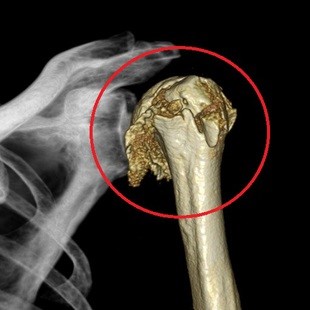

短時間で一度に広範囲の撮影が可能で、多くの情報を得られることがCT検査の大きな特徴です。CT検査は特に、脳出血、肺炎や肺がん、骨折、腹部疾患の診断に有用です。また、骨折部位を立体的に確認できる3D画像作成にも活用され、治療方針の決定や手術計画にも役立てられています。

骨折・3D画像

関節(膝・肩など)